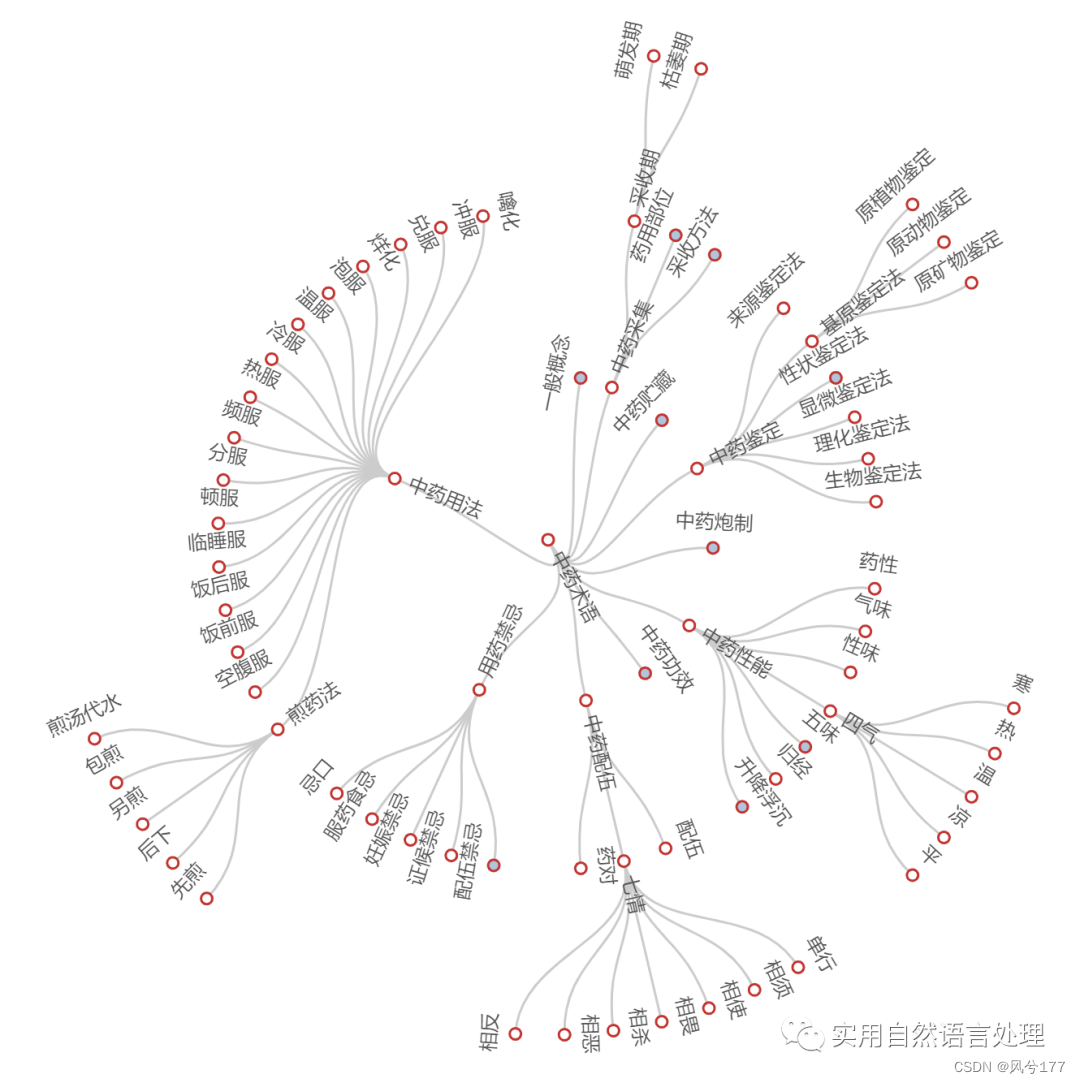

2.4 中药术语知识图谱可视化

中医术语知识为层次结构,其树形图展示如下。

环形树图(部分节点展开)